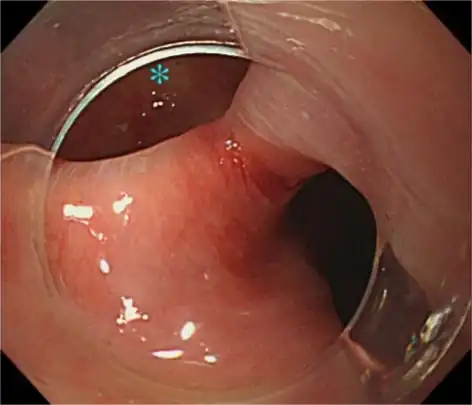

Hood-assisted upper endoscopy clarified the border of Zenker diverticulum ( and upper esophagus) -